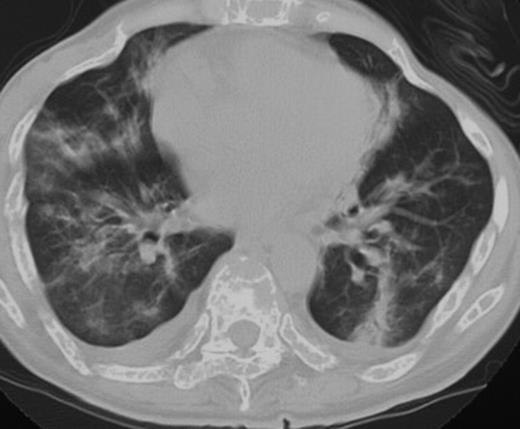

A 48-year-old woman with multiple myeloma, IgD type, underwent unrelated bone marrow transplantation following fludarabine, melphalan, and total-body irradiation in 2002.8 She had no history of smoking or pulmonary problems. The primary disease recurred 3 months after transplantation, and she received 1.3 mg/m2 bortezomib twice a week for 2 weeks. Pretreatment examination failed to show any evidence of infection, and her PS was 1.7 She developed high-grade fever on the day of the fourth dose of bortezomib and severe respiratory failure 5 days after the fourth dose. Chest CT showed bilateral infiltrates with pleural effusions (Figure 2). Peripheral leukocyte count was 4.5 ×109/L (4500/μL), and she had no signs of infection. She received alendronate, fluconazole, allopurinol, trimethoprim/sulfamethoxazole, and famotidine. Her respiratory failure resolved with 500 mg methylprednisolone, and the infiltrates on the chest CT improved. Due to rapid disease progression, she was again treated with bortezomib in combination with 100 mg hydrocortisone with each dose. The disease was well controlled after 11 doses of bortezomib. She never developed respiratory failure.

Computed tomography of the chest on the day of the fourth dose of bortezomib showed bilateral pleural effusion and pulmonary infiltrates (patient 3).